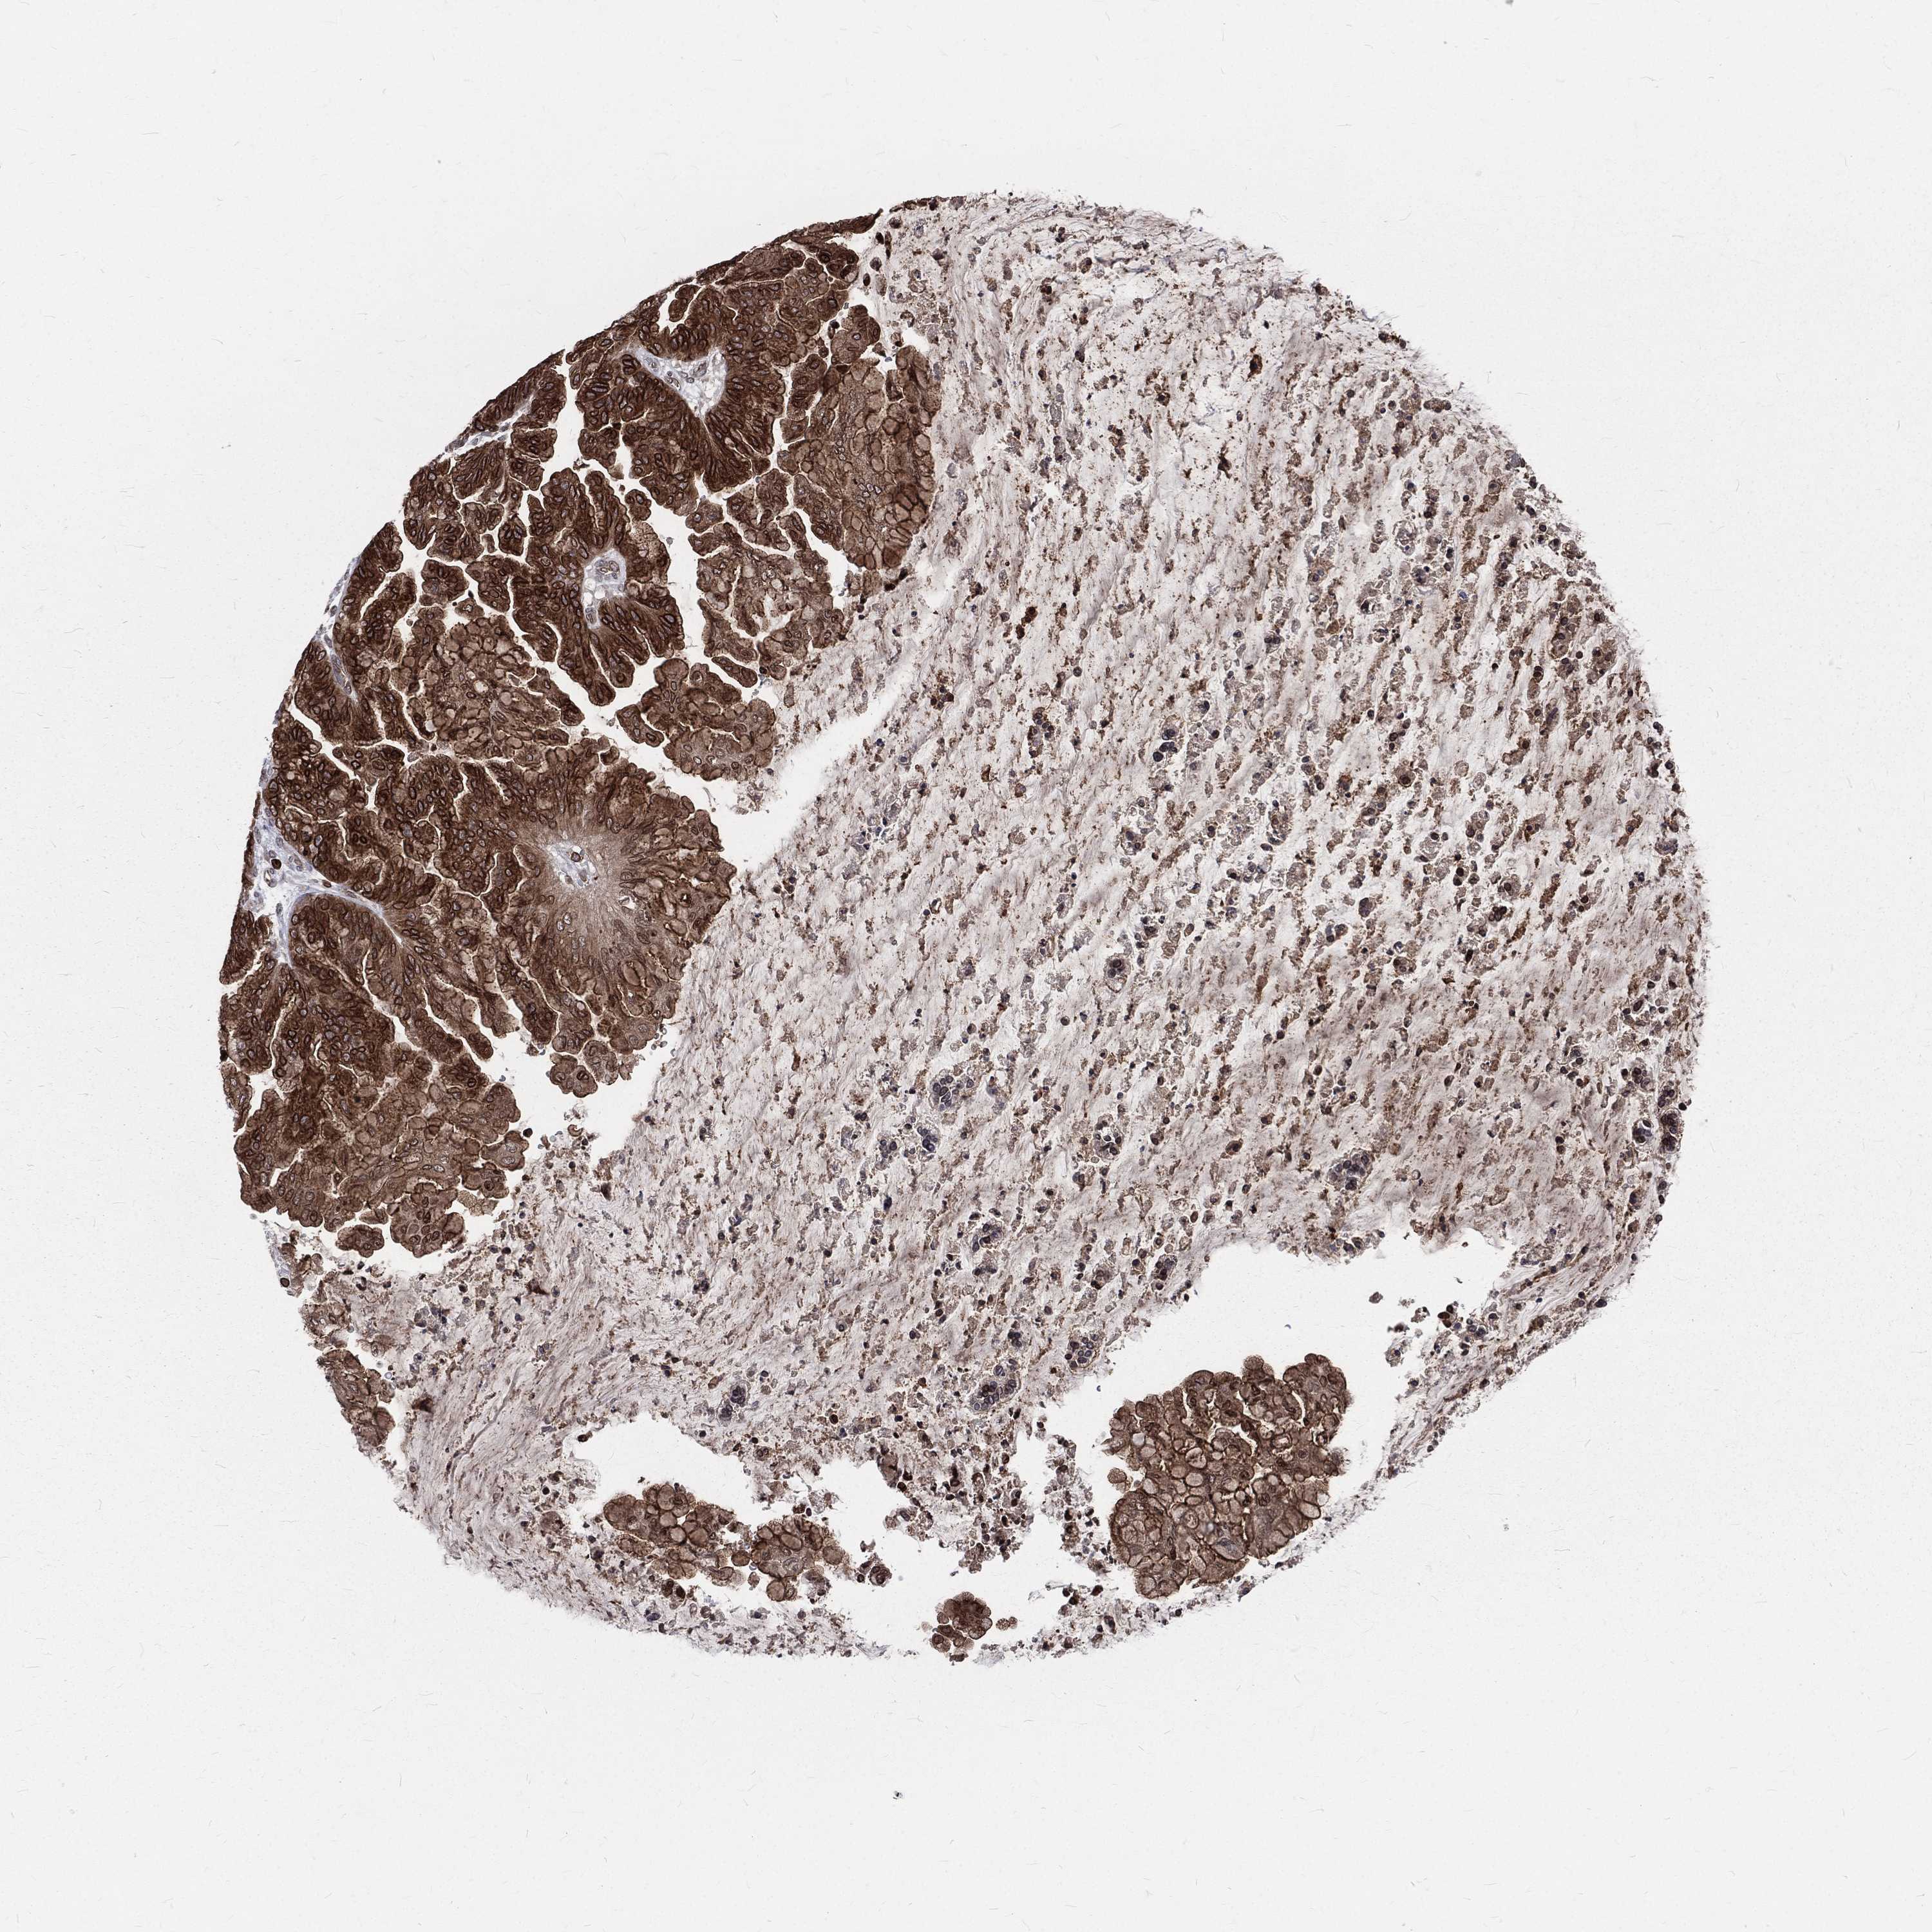

OVARIAN CANCER - Protein expressioni

A mouse-over function shows sample information and annotation data. Click on an image to view it in a full screen mode. Samples can be filtered based on level of antibody staining by selecting one or several of the following categories: high, medium, low and not detected. The assay and annotation is described here.

Note that samples used for immunohistochemistry by the Human Protein Atlas do not correspond to samples in the TCGA dataset.

Antibody stainingi

Antibody staining in the annotated cell types in the current human tissue is reported as not detected, low, medium, or high, based on conventional immunohistochemistry profiling in selected tissues. This score is based on the combination of the staining intensity and fraction of stained cells.

Each image is clickable and will lead to virtual microscopy that enables deeper exploration of all samples and also displays staining intensity scores, fraction scores and subcellular localization as well as patient and tissue information for each sample.

Antibody HPA049840

Antibody HPA062236

Staining

High

Medium

Low

Not detected

Location

Nuclear

Cytoplasmic/membranous

Cytoplasmic/membranous,nuclear

None

Cystadenocarcinoma, serous, NOS

Carcinoma, endometroid

Cystadenocarcinoma, mucinous, NOS

Carcinoma, NOS